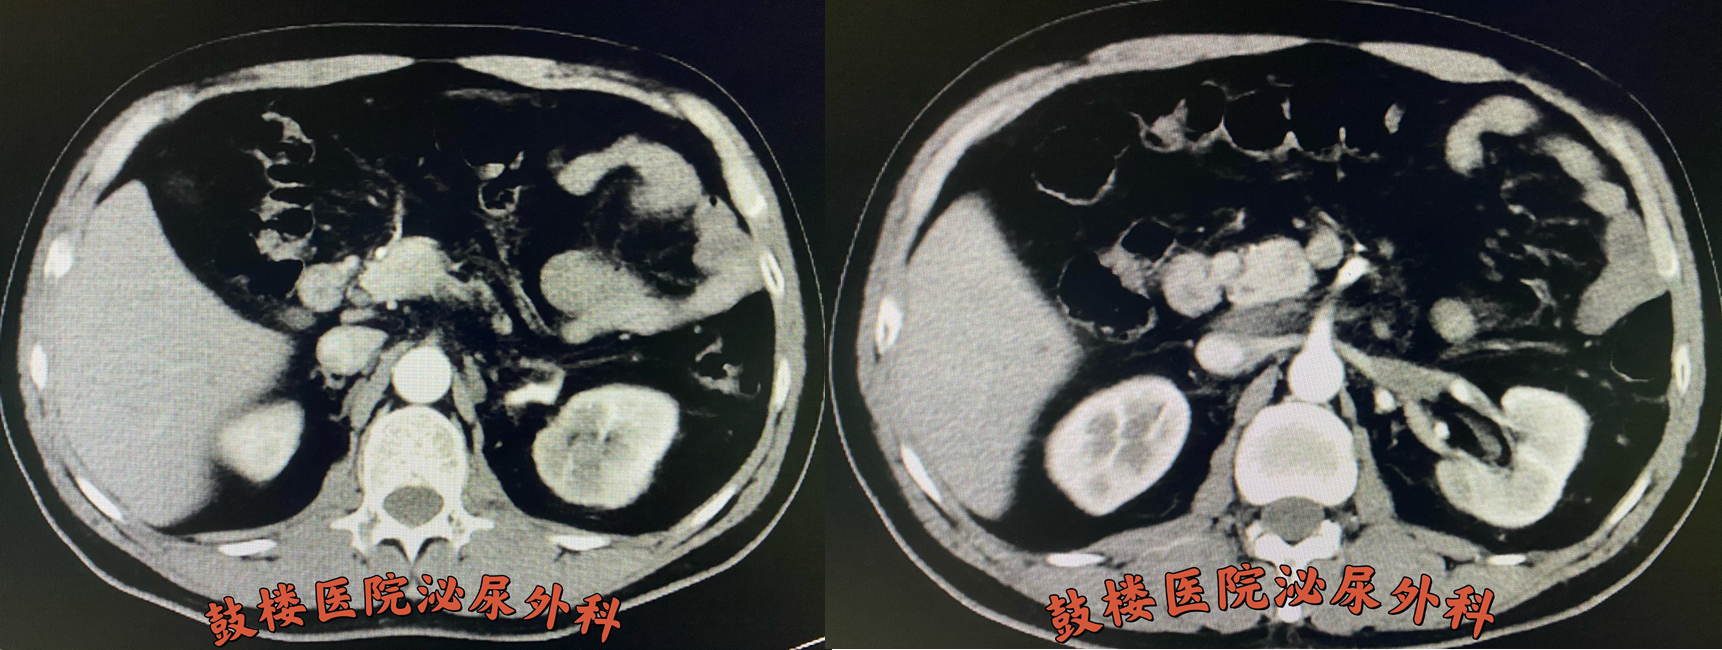

鼓楼医院泌尿外科郭宏骞主任、纪长威副主任医师、张顺副主任医师针对李先生的病情进行多次会诊后制定了新辅助治疗后行根治性切除手术的方案并安排他入组了鼓楼医院领衔的“阿昔替尼+PD-1”新辅助治疗项目,该项目使患者有机会用到目前最先进的PD-1免疫疗法,且PD-1药物完全免费。按预定计划进行三个周期的治疗后,李先生无明显不良反应,仅仅两个月的时间,复查效果令人惊喜。李先生的肾脏肿瘤病灶几乎消失不见,癌栓也明显缩退,预期的手术风险和难度明显降低。

新辅助治疗后左肾肿瘤几乎消失,左肾静脉瘤栓明显缩小。